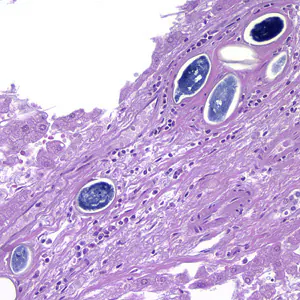

Schistosoma spp. eggs in tissue, stained with hematoxylin and eosin (H&E).

Cross-sections of human tissues with Schistosoma spp. adults.